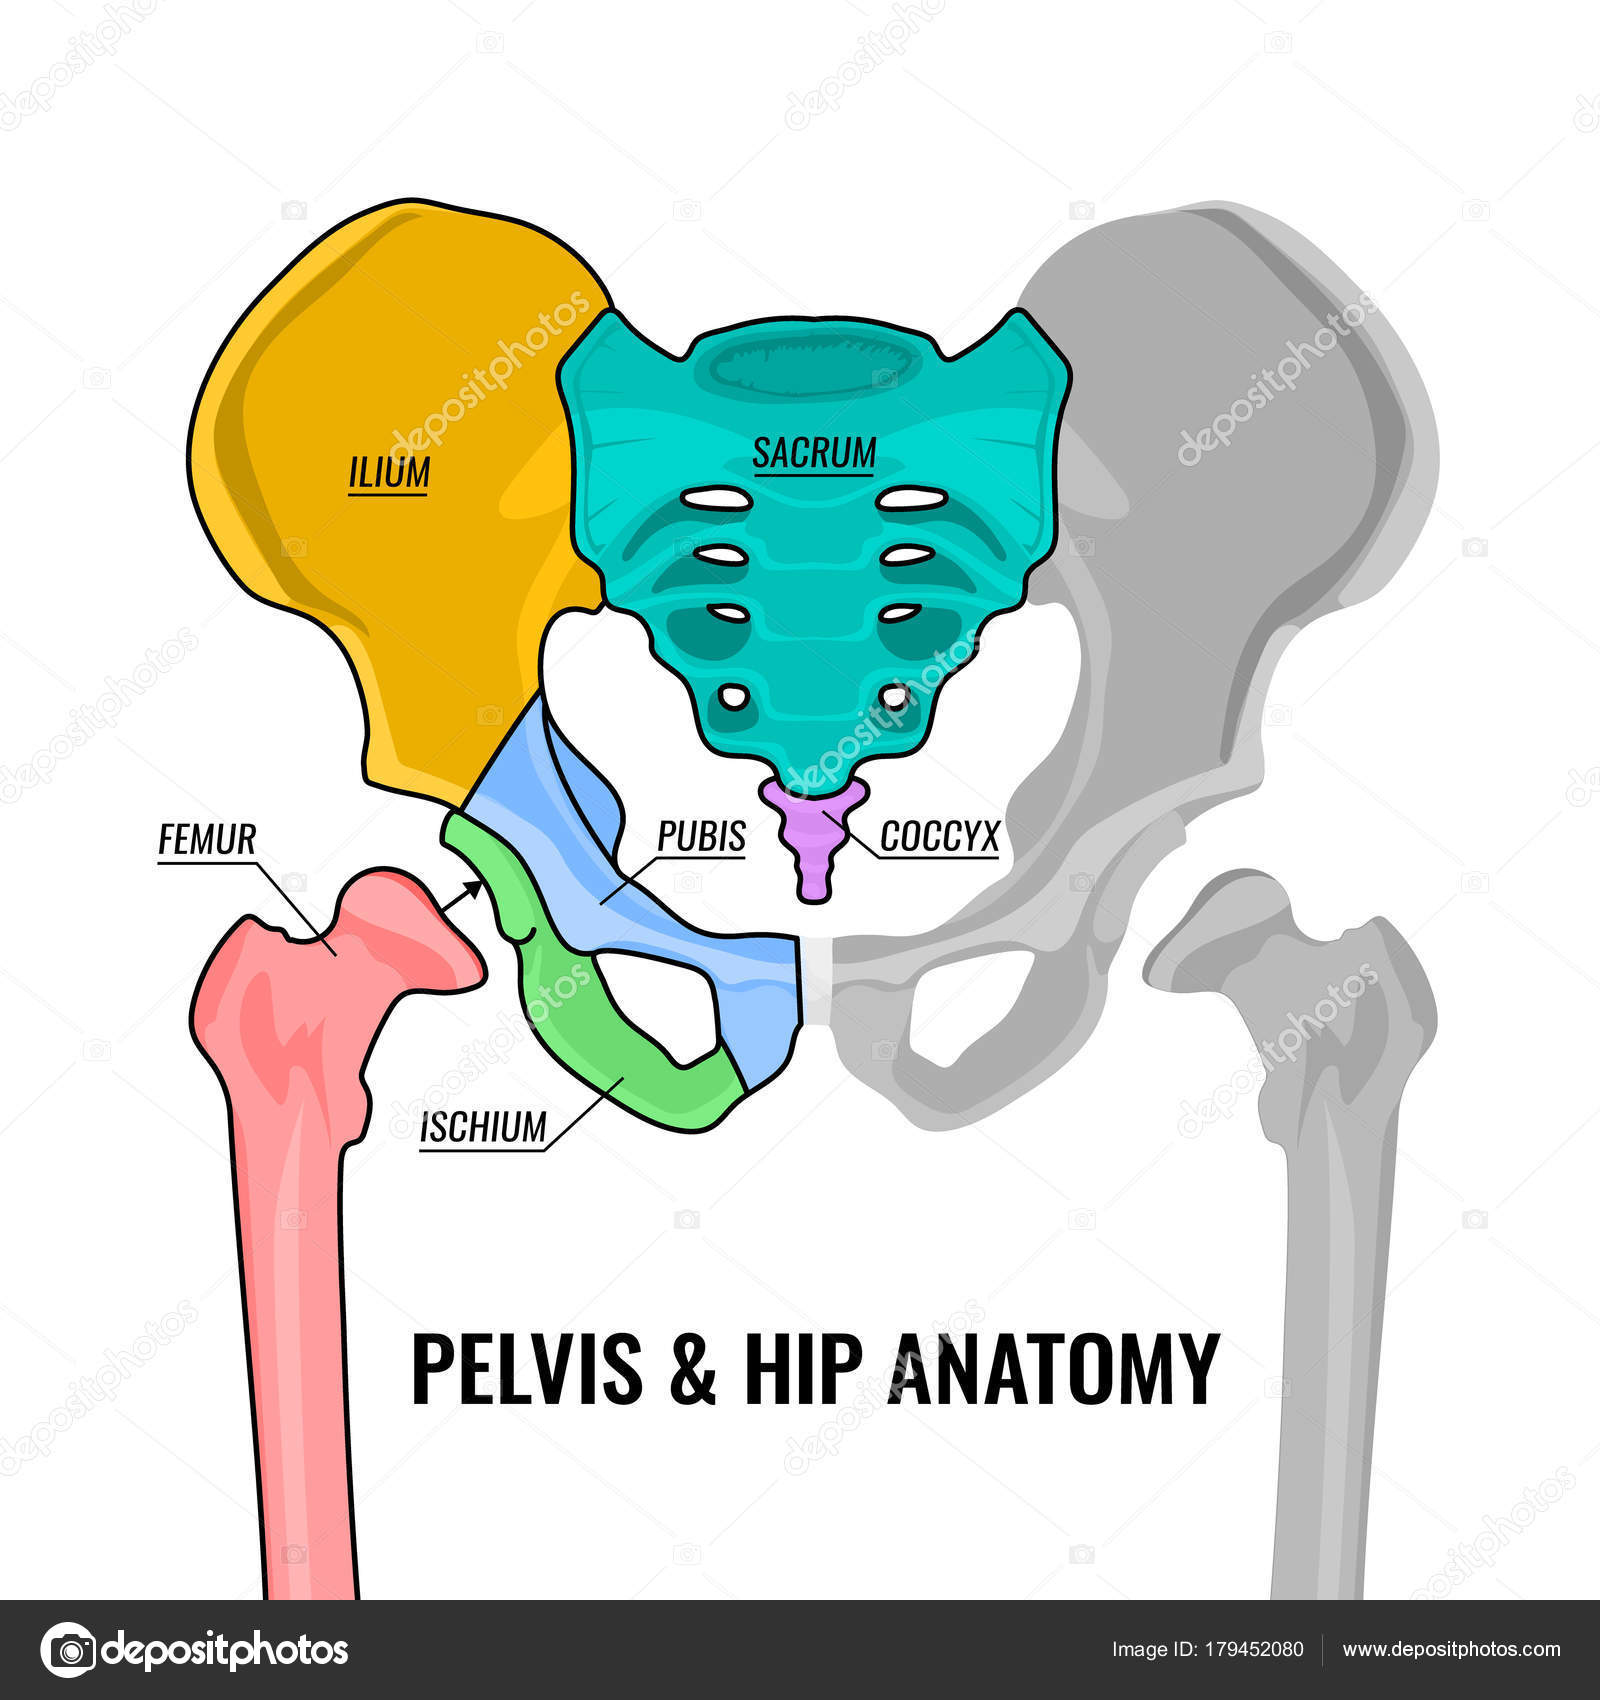

首先,为大家科普一下骨盆和髋关节的骨骼组成,如下图:

骨盆和双髋关节骨骼结构模式图

pelvis & hip anatomy骨盆和髋关节骨骼解剖组成:femur股骨,pubis耻骨,ischium坐骨,ilium髂骨,sacrum骶骨,coccyx尾骨